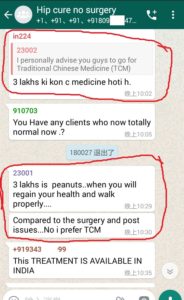

1. The Gentleman in Kenya started his treatment at his home April 27, now he said: (will update his more progresses soon)

3. The gentleman in India just started May, 2019. Actually he started on April 28, 2019 but he used it in wrong way and got less effects, ONLY on May 8, 2019 during our follow-up, we found his wrong-doing, and then corrected him. ONLY in 2 days, his pains significantly reduced!!!!